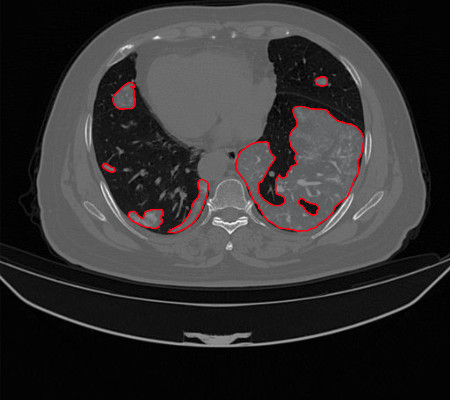

O sistema irá auxiliar os especialistas na triagem/diagnóstico da COVID-19 por meio de imagens de tomografia computadorizada.

O uso da tomografia computadorizada (TC) tem se mostrado uma abordagem promissora para a avaliação de pacientes suspeitos com COVID-19, visto que há uma grande procura para os testes tradicionais. No entanto, é necessário que a tomografia computadorizada seja analisada por um especialista. Pensando nisso, os pesquisadores estão desenvolvendo métodos computacionais que pretendem integrar um software que irá auxiliar os médicos no diagnóstico da Covid-19, como na triagem de pacientes e também promovendo uma segunda opinião.

“A ideia é usar sistema CAD de diagnóstico auxiliado por computador, para minimizar os problemas gerados pela complexidade de análise das tomografias computadorizadas. Dentre os objetivos esperados nesse estudo destacamos: revisão do estado da arte, considerando o desenvolvimento de sistemas CAD para auxiliar diagnóstico médico; desenvolvimento de métodos para caracterizar e classificar imagens de TC usando redes neurais convolucionais; e a aplicação do método desenvolvido para realização da classificação das imagens”, explica o Prof. Dr. Ricardo Rabêlo, coordenador do estudo e lotado no Departamento de Computação da UFPI, em Teresina.

Os pesquisadores analisaram um conjunto de 708 imagens de tomografia computadorizada, sendo 312 de pessoas com Covid-19 e 396 de pessoas que não possuem a doença. “O método que a gente vem desenvolvendo, consiste na utilização de arquiteturas de inteligência computacional, especificamente as abordagens deep learning (aprendizado profundo). Essas abordagens são técnicas computacionais que analisam as imagens extraindo valores destas. Estes valores, vão fornecer aprendizados ao método desenvolvido, que vai permitir apontar se as imagens da TC têm ou não suspeição de Covid-19", diz o Prof. Dr. Antônio Oseas, do curso de Sistemas de Informação da UFPI, em Picos.